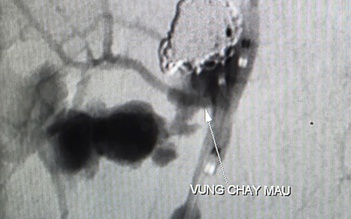

Cứu sống ca xuất huyết tiêu hóa từ ruột non nguy kịch

Phẫu thuật cứu sống bệnh nhân bị xuất huyết tiêu hóa ồ ạt hiếm gặp